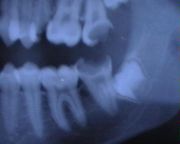

caries à un stade avancé (sur 2e molaires sup et inf)

Les signes peceptibles de la carie n'apparaissent pas tout de suite. Les premiers signes peuvent apparaître une fois que la carie a atteint la dentine. Mais parfois la douleur ne survient que très tardivement. C'est pourquoi il est vivement conseillé de ne pas attendre d'avoir mal pour consulter un dentiste.

Cette infection peut être chronique : granulome péri-apical chronique ou kyste (ou desmodontite apicale chronique). L'infection évolue alors souvent à bas bruit pendant plusieurs mois voire plusieurs années, et n'est parfois détectée que par un contrôle radiographique de routine. Cette infection peut aussi être aiguë : abcès péri-apical aigu (ou desmodontite apicale aiguë). (voir : endodontie) Si un traitement n'est toujours pas entrepris, l'infection continue à se propager. Les ostéites et cellulites peuvent préluder à l'envahissement bactérien par voie sanguine : c'est la septicémie. Le pronostic vital est alors engagé.